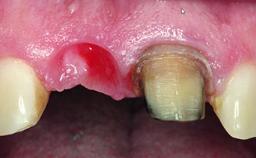

A 32-year-old female Caucasian patient with a compromised maxillary right central incisor was referred to us by a general dentist. Her chief complaints were discomfort and mobility of tooth 11 with unsatisfactory esthetics due to discoloration. The patient reported a previous trauma, some years earlier, as the origin of pathology on the afflicted tooth. Anamnesis was negative for any other dental or periodontal pathology in the remaining dentition. The patient did not take any medication and reported to be a light smoker (5–10 cigs/day). She had high esthetic expectations of her treatment. The extraoral examination revealed a high smile line with full exposure of her maxillary teeth and surrounding soft tissue in the area between the second premolars.

Bone Volume | Deficient horizontally, requiring prior grafting |